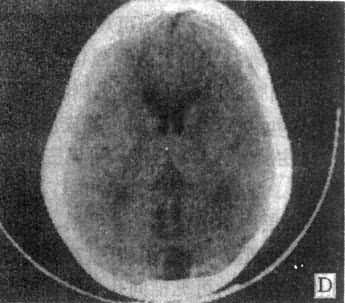

MRI 适宜于观察CT扫描为等密度的亚急性脑内血肿,已如前述。脑梗塞的发现MRI比CT扫描要早,一般起病后6小时MRI即可出现异常。脑干和小脑腔隙性梗塞灶的探测,MRI明显优于CT。脑梗塞灶在T1WI上呈低信号,在T2WI上呈高信号(图5-1-6C、D)。

图5-1-6 MRI扫描SE序列图像

在矢状面(A)和冠状面(B)T1WI可见垂体肿块向鞍上延伸,呈等信号区(→);在横断面T1WI(C)和T2WI(D)上分别可见左枕和右基底节区脑梗塞灶呈低和高信号区(→);在矢状面T1WI(E)和横断面T2WI(F)上,可见基底动脉瘤环形影,其内为低信号和高信号区,高信号区为瘤内血栓形成(→)